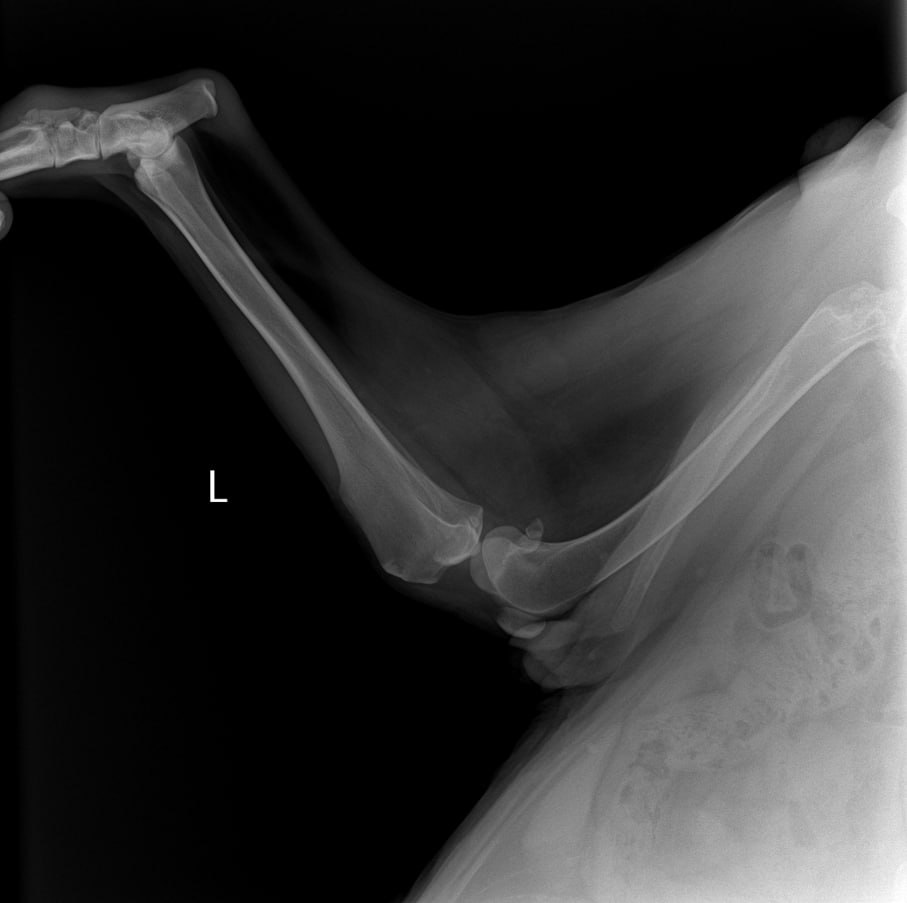

Рентген лапы, которая болит

Зона операции в снимок не попала....но со слов врача все нормально. То что видно - чисто....придется поверить, но так как шов подтекает, антиюиотик попробуем заменить на клиндомицин.

Сильнейший коксартроз тбс на больной лапе.....который не заметили на первичных осмотрах....зато настаивали в необходимости кастрации. В результате изменения положения лапы, нагрузки - воспаление и боль.